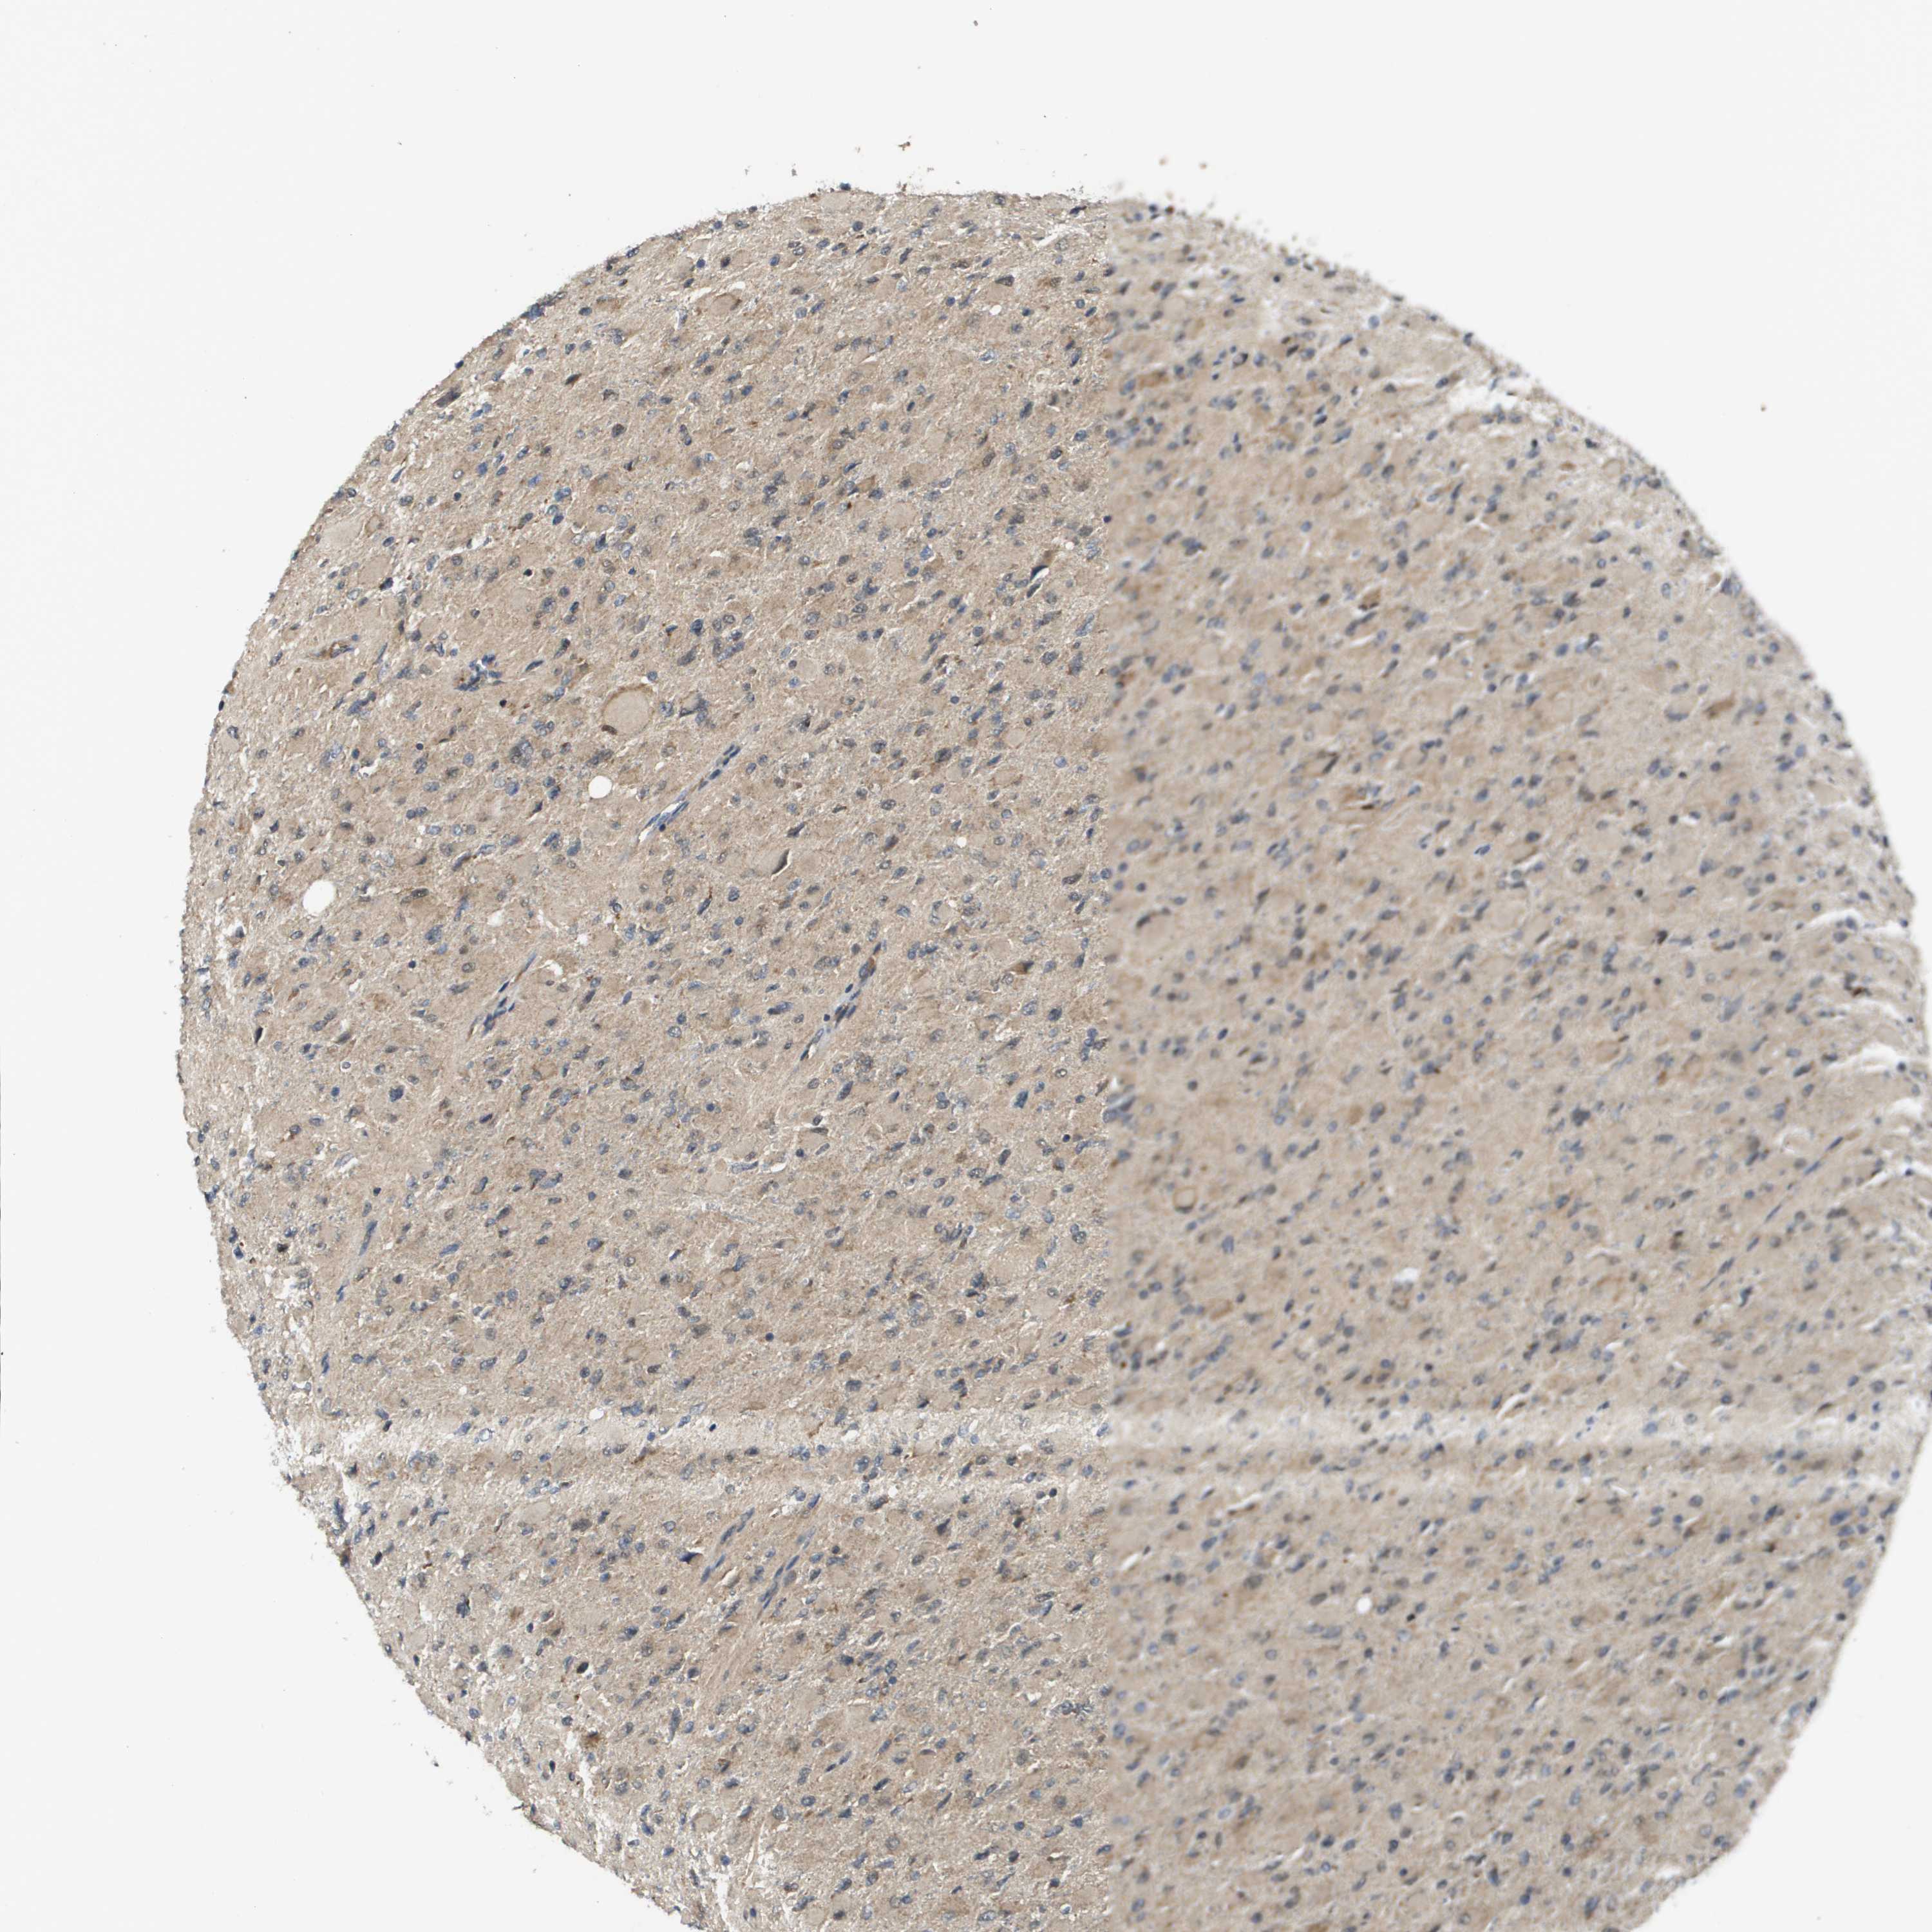

GLIOMA - Protein expressioni

A mouse-over function shows sample information and annotation data. Click on an image to view it in a full screen mode. Samples can be filtered based on level of antibody staining by selecting one or several of the following categories: high, medium, low and not detected. The assay and annotation is described here.

Note that samples used for immunohistochemistry by the Human Protein Atlas do not correspond to samples in the TCGA dataset.

Antibody stainingi

Antibody staining in the annotated cell types in the current human tissue is reported as not detected, low, medium, or high, based on conventional immunohistochemistry profiling in selected tissues. This score is based on the combination of the staining intensity and fraction of stained cells.

Each image is clickable and will lead to virtual microscopy that enables deeper exploration of all samples and also displays staining intensity scores, fraction scores and subcellular localization as well as patient and tissue information for each sample.

Antibody CAB017036

Staining

High

Medium

Low

Not detected

Intensity

Strong

Moderate

Weak

Negative

Quantity

>75%

75%-25%

<25%

None

Location

Nuclear

Cytoplasmic/membranous

Cytoplasmic/membranous,nuclear

Glioma, malignant, High grade

Glioma, malignant, Low grade